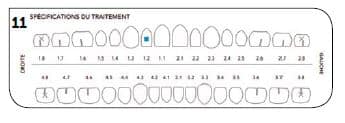

Au final, une ultime série d’aligneurs fut réalisée pour terminer le bon positionnement des dents du patient (Fig.11).

Pour cette partie du traitement : seulement 7 aligneurs pour le maxillaire avec des gouttières passives pour la mandibule (Fig.12 à 17).